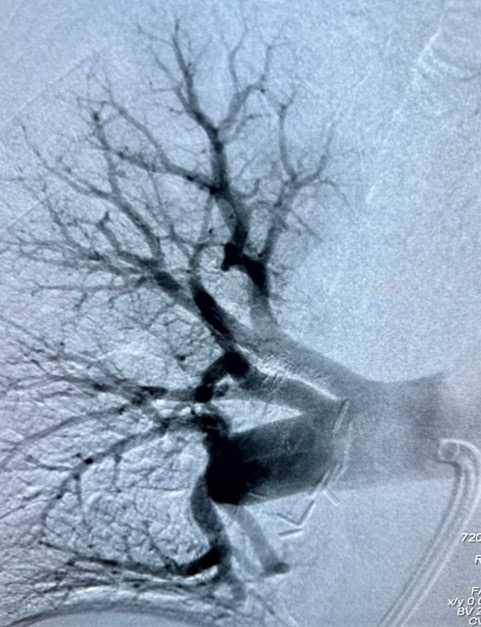

La angiografía final (un estudio con contraste) mostró que las arterias pulmonares estaban libres de obstrucciones y el flujo sanguíneo era adecuado.